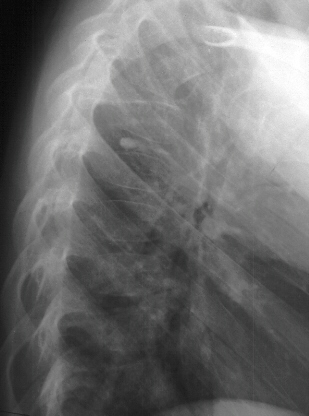

Patient is a 4 year old male who developed the insidious onset of neck pain and stiffness 4 days prior to admission. Over the intervening period, the patient suffered from worsening of his symptoms which led to increasing irritability and difficulty sleeping. On the day of admission, he was seen by a local pediatrician for severe neck pain. It was observed that his head was in a fixed position just slightly right of midline. The patient's past medical history was remarkable for two recent self-limited episodes of hives and urticaria on his trunk and extremities that was treated with prednisone. There was vague history of remote trauma about one month previously when the patient had been "horsing" around with his brother. The child had no evidence of a viral prodrome, constitutional symptoms or travel history. He was sent to a local hospital where radiographs of the cervical spine demonstrated calcifications in the C3-4 and C5-6 intervertebral disc spaces . Neurological exam was normal. The child's pain was refractory to morphine treatment and he was transferred to A.I. for the management of his intractable pain. On arrival, his physical exam was unchanged. Blood work revealed a WBC count of 12.7K with 75% PMNs and an ESR of 80. Radiographs of spine showed the presence of an addition calcification in his thoracic spine . He was treated with oral valium and a soft cervical collar. Over the ensuing 24 hrs the child demonstrated marked improvement of his symptoms and was switched to motrin. He was subsequently discharged.

It is most common in the cervical spine, where it is especially symptomatic. Asymptomatic lesions have been detected in the thoracic spine on routine chest radiographs.

XRAYS

The number of calcified discs varied from 1 to 12 (mean 1.69) . Symptomatic calcified discs are most common at C6-7. Radiologic examination shows images of calcium density in the normally radiolucent intervertebral discs. Anterior or posterior protrusion can be observed. The lesions demonstrate high density on CT and low signal intensity on MRI.